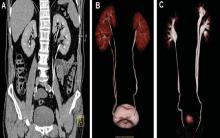

Hidronefroza congenitală la copii

Hidronefroza se caracterizează prin retenția de urină în bazinet (segmentul colector format prin reuniunea calicelor și care se prelungește cu ureterul), produsă de un obstacol la nivelul tractului urinar, urmată de dilatarea bazinetului, calicelor (conducte renale a rinichiului care culeg urina), iar în cazuri mai avansate prin atrofia parenchimului renal şi diminuarea progresivă a funcţiilor de bază ale rinichilor.